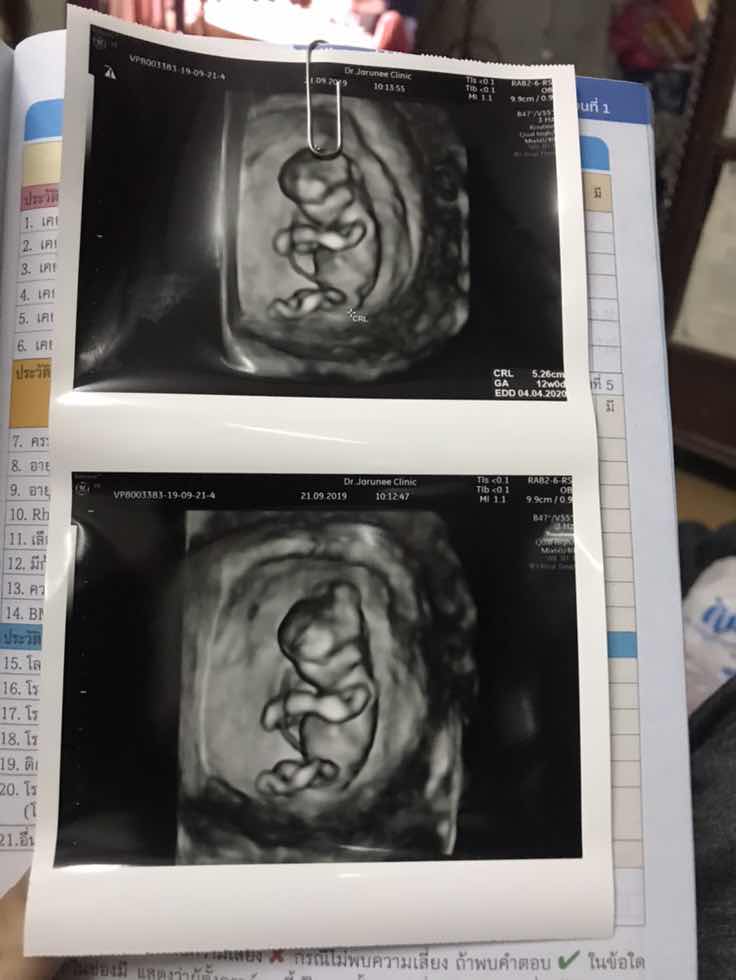

12wคะ ตอนนี้13+4